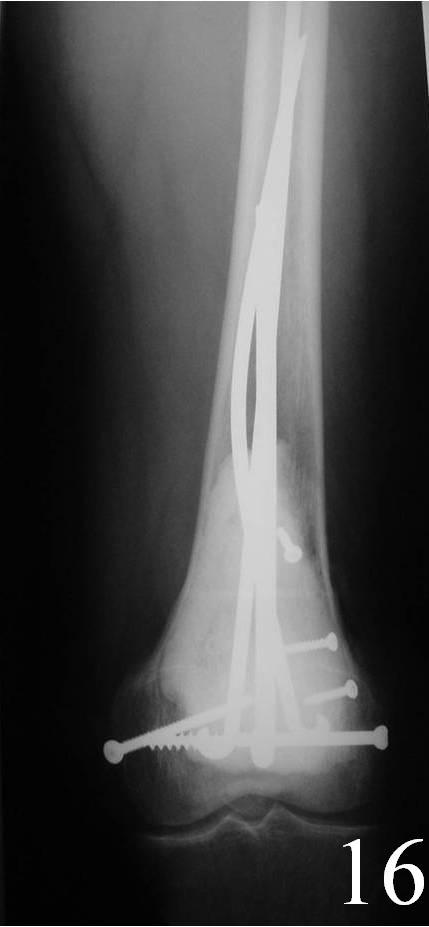

o Curettage, cement and possible internal fixation with hardware (Fig. 13, 14, 16)

Fig. 16 AP Xray of distal femur demonstrates fixation with Rush rods and cement.